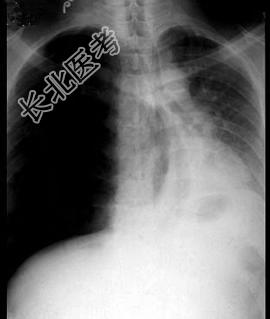

- 单项选择题男,35岁, 被汽车撞伤右胸已经24小时,颜面口唇苍白, 皮肤湿冷,心律120次/分, 血压12/9、33kPa(90/70mmHg),呼吸困难逐渐加重, 气管左移,右侧叩诊高度鼓音, 右侧胸穿未抽出血液,胸部X线检查如图。最可能的诊断是 ( )

C、张力性气胸